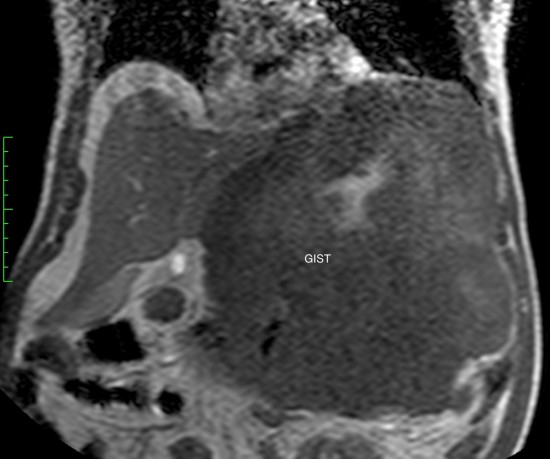

Гастроинтестинальная стромальная опухоль гигантских размеров, исходящая из большой кривизны желудка